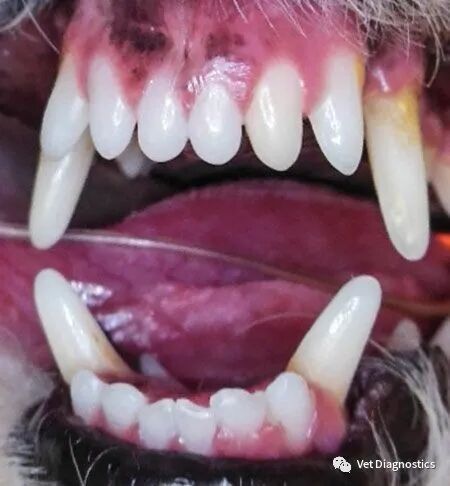

获得长期积极结果的更健康的牙科方法是首先检查有意识的患者(包括口腔),然后在全身麻醉下进行逐牙检查(包括探查和口腔内x光片)。如果牙齿和支撑结构状态良好,继续下一颗牙齿。如果没有,诊断病理并制定治疗和预防计划(图1A-1D)。

图1B.牙周探针插入狗的部分萌出的左下颌犬齿之前。

图1C.10mm牙周袋;牙龈切除术、牙龈粘膜手术或拔牙指征。